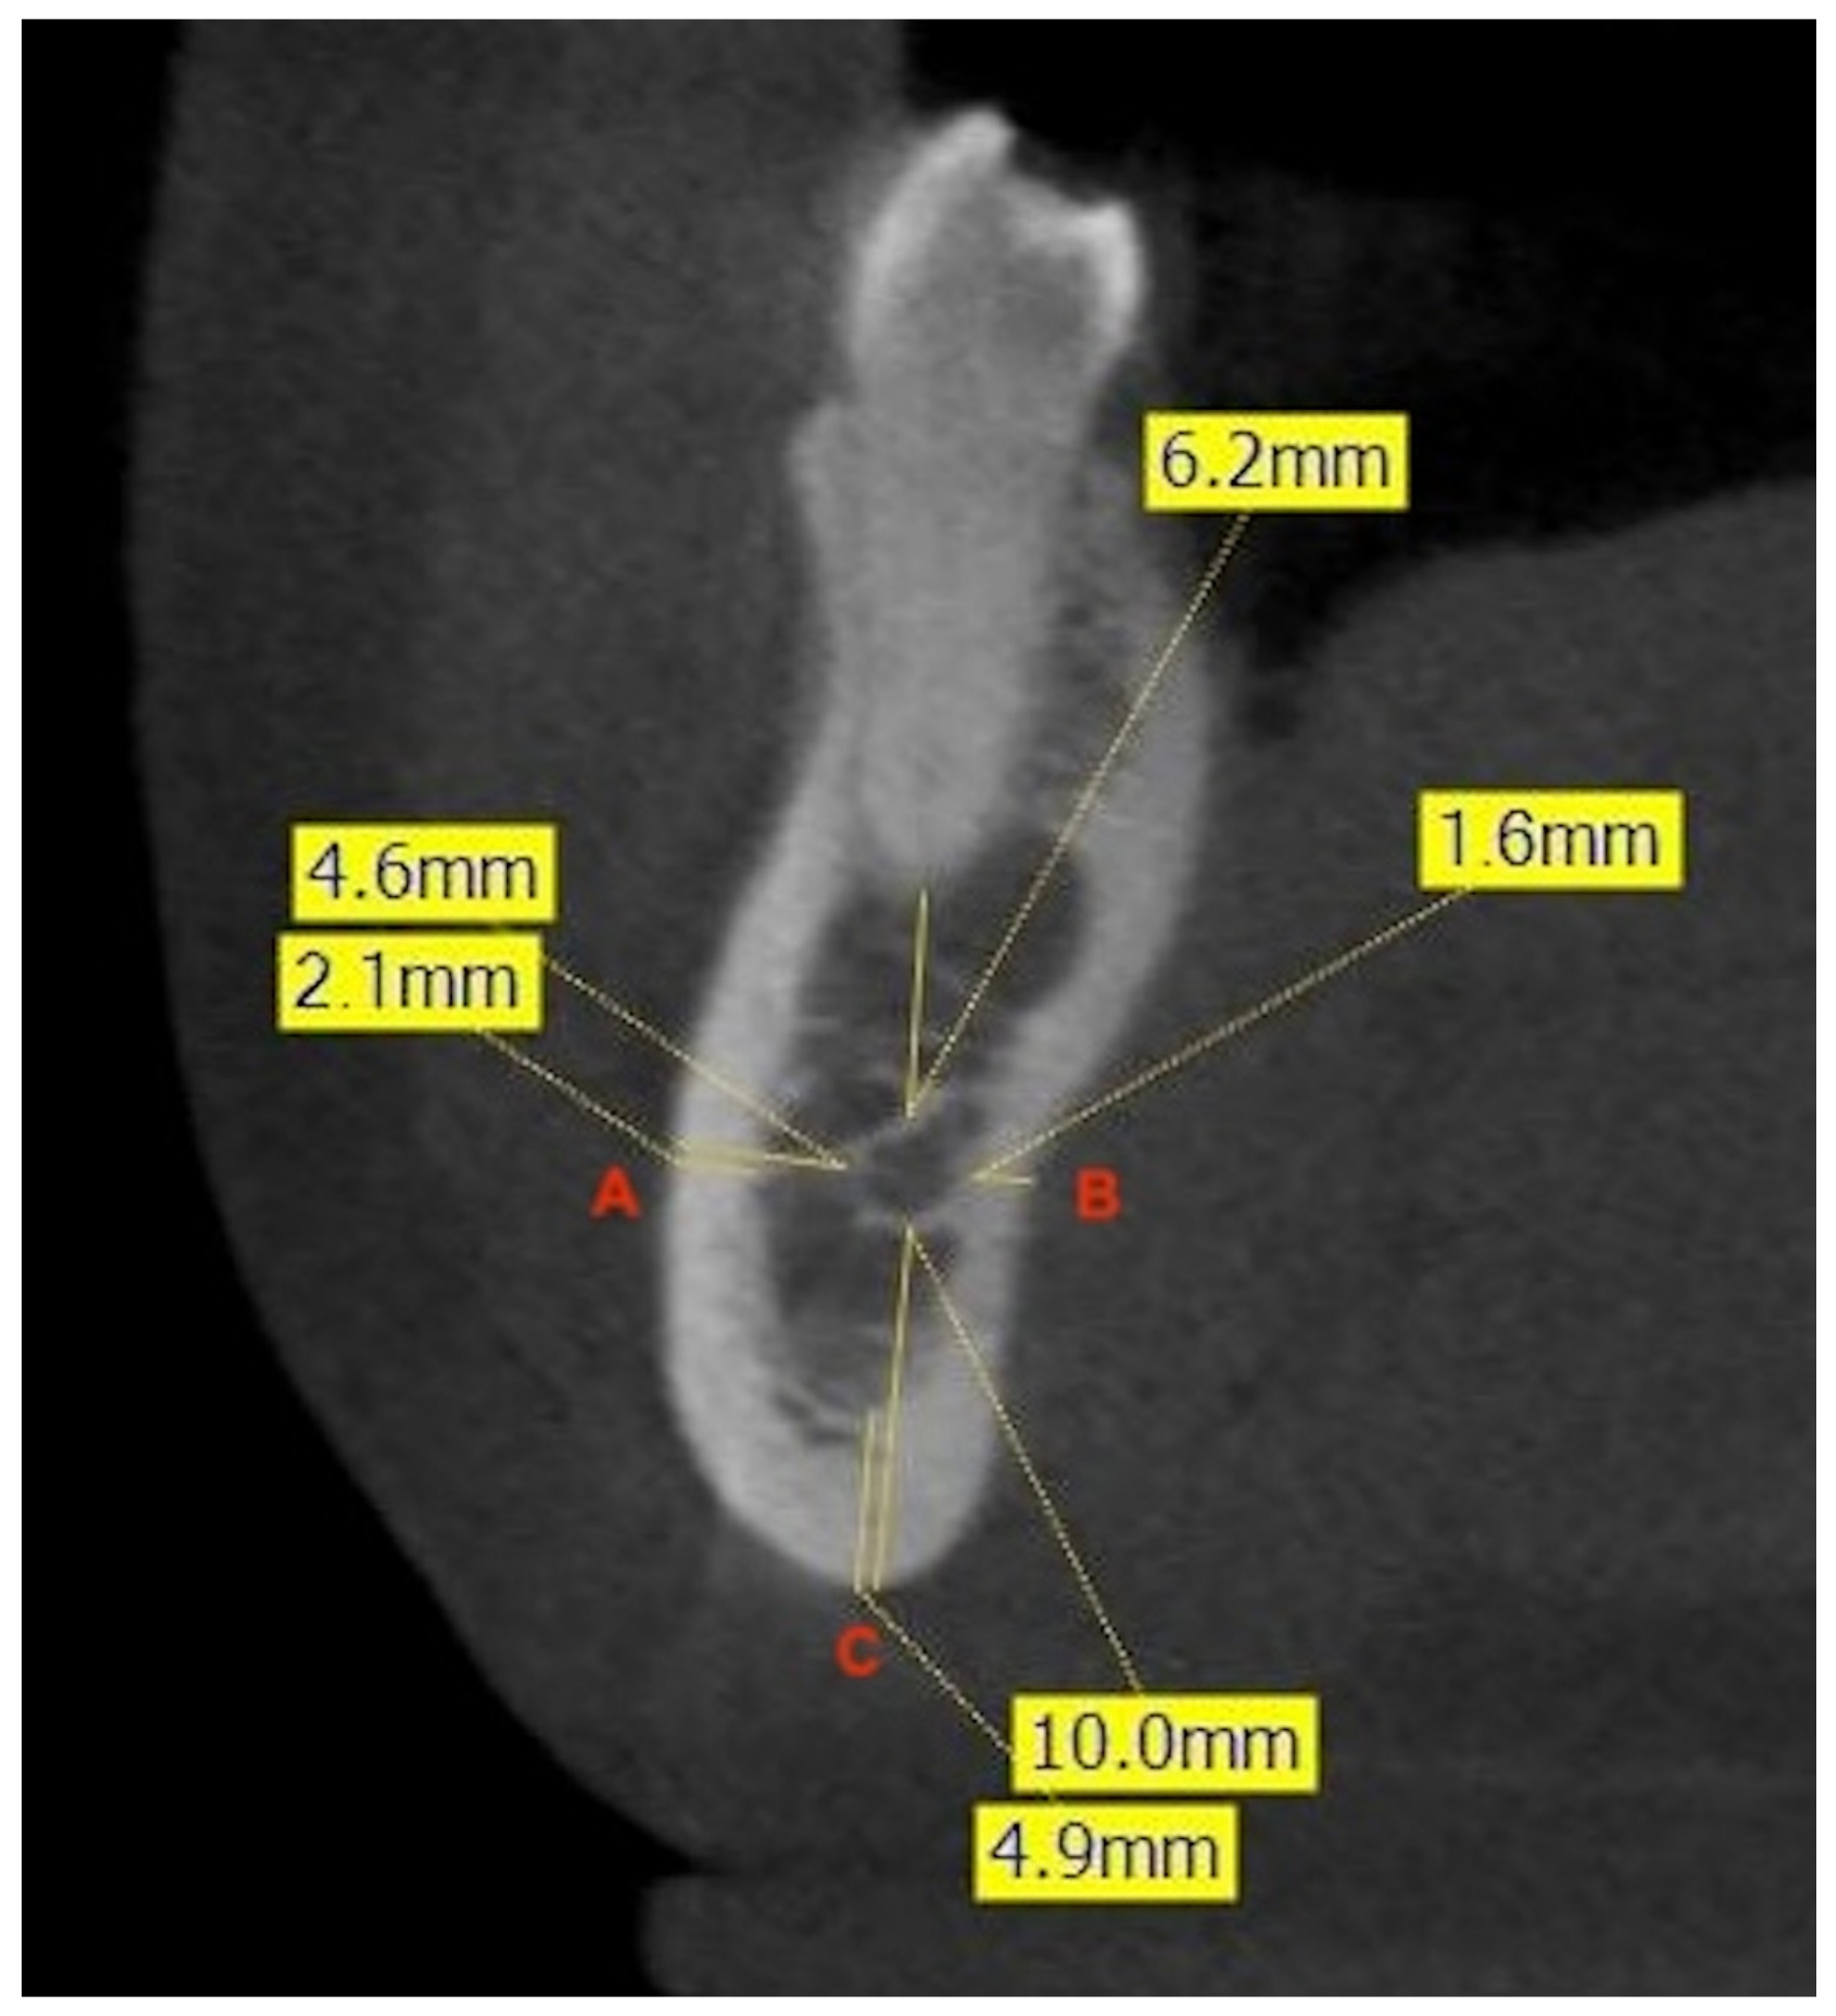

To evaluate the bone thickness surrounding the MC, the major axes of the mandibular teeth were fixed, and three lines were drawn to three different points. Point A was fixed on the vestibular cortex, point B on the lingual cortex, and point C on the base of the mandible. Then, the average distances from these points to the MC were measured. After this recording, cortical thicknesses were measured to differentiate between medullary and cortical bone. Thicknesses were measured in relation to the major axis of the 2MPM, in the interradicular zone of the 1M, and in the interradicular zone of the 2M (Figure 2).

Figure 2. Example of measurement of the shortest linear distances (mm) at the level of the right second premolar. The frontal CBCT image shows the distance from the most buccal (A) and lingual (B) aspects of the canal to the corresponding cortical plates of the mandible, and the minimum linear distance between the inferior aspect of the canal and the inferior border of the mandible (C). The measurement of the thickness of the cortical bone at each point is also illustrated.